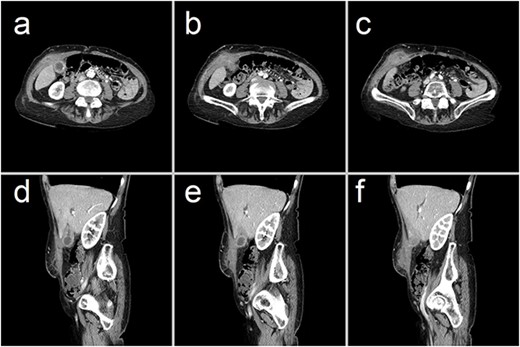

A 75-year-old woman from a nursing home presented to the emergency department with a 3-week history of a painful right-sided abdominal lump. She was otherwise systemically well. Her medical history was notable for end-stage chronic obstructive pulmonary disease requiring permanent home oxygen, lung cancer, and chronic cholecystitis. On presentation, all her vitals were normal. Examination revealed an indurated, tender, irreducible mass in the right hypochondrium with overlying cellulitis. Her white cell count was 9.3 mmol/L and C-reactive protein was 45 mg/L. CT scan revealed a complex collection in the right anterior abdominal wall, contiguous with a thickened gallbladder, consistent with an abdominal wall abscess complicating perforated acute-on-chronic cholecystitis (Fig. 1).

Representative CT images showing (a–c) axial and (d–f) sagittal views of a 47 × 23 × 66 mm complex collection within the right anterior abdominal wall, consisting of fluid and phlegmonous components. This collection is contiguous with a thick-walled gallbladder that contains calculi. These findings are consistent with an abdominal wall abscess complicating acute-on-chronic cholecystitis with extraperitoneal perforation.